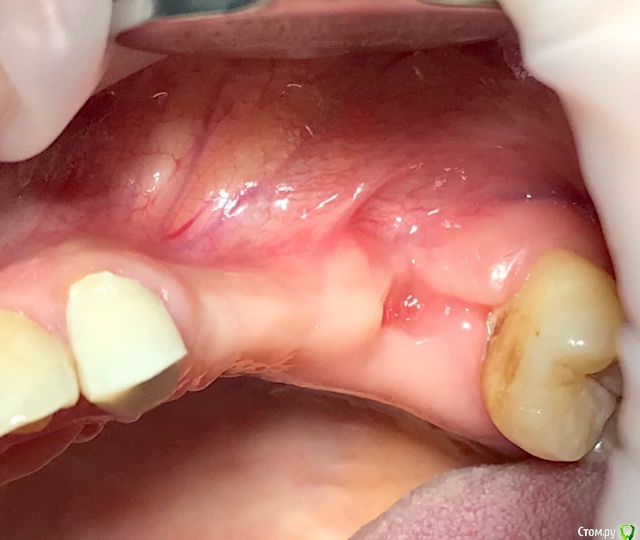

колесников Опубликовано 27 сентября, 2019 Автор Поделиться Опубликовано 27 сентября, 2019 Улучшение объема и качества мягких тканей в пришеечной области у ранее поставленных имплантов ,посредством тоннельной костной пластики. Объём 0,5г. Вид через 6 мес. 3 Ссылка на комментарий